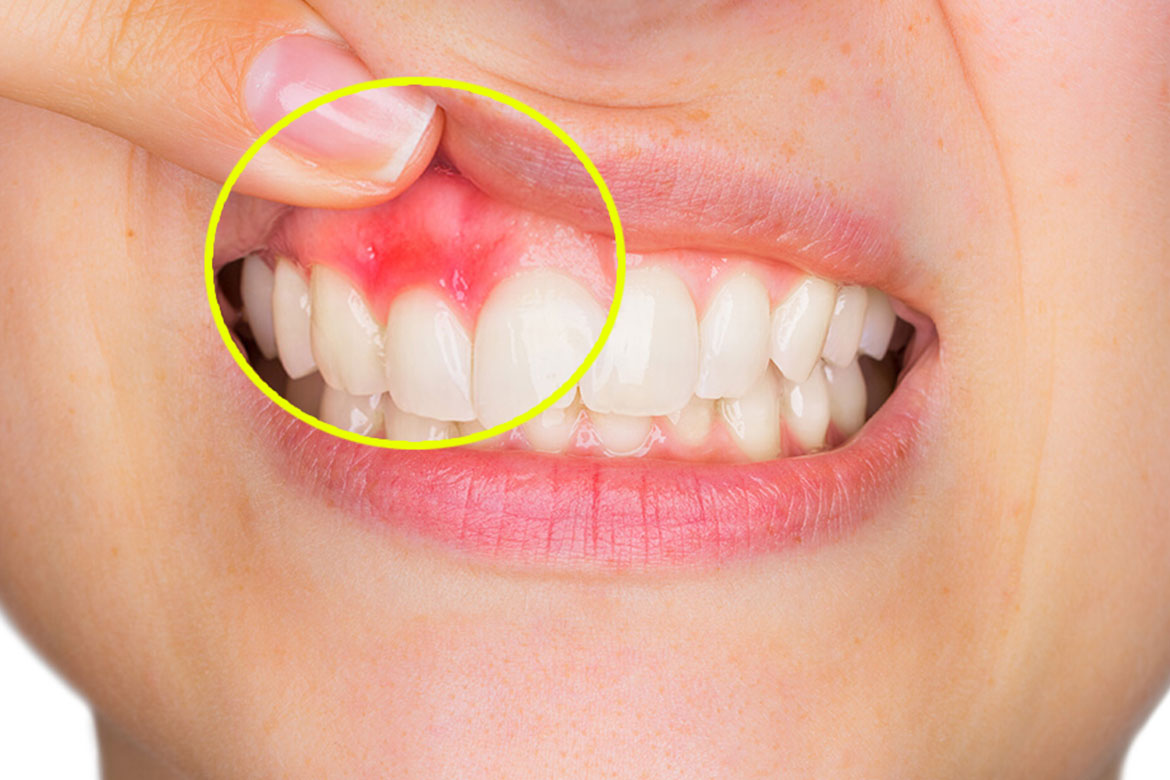

Maladies gingivales